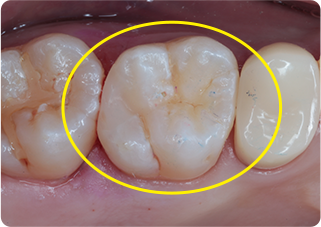

セラミックアンレー症例①

術前

むし歯除去

ラバーダム防湿

術後

| 主訴 | むし歯の治療をしたい |

|---|---|

| 治療期間/回数 | 2週間、2回 |

| 価格(税込) | 77,000円(税込) |

| リスク・副作用 | セラミックの破損、一時的な知覚過敏が生じる場合がある |

| ポイント | ラバーダム防湿をし、唾液や呼気の侵入を防ぎ湿度を下げることで、セラミックの接着力の向上を計った。接着力の向上により、脱離や破折の予防になる。 |